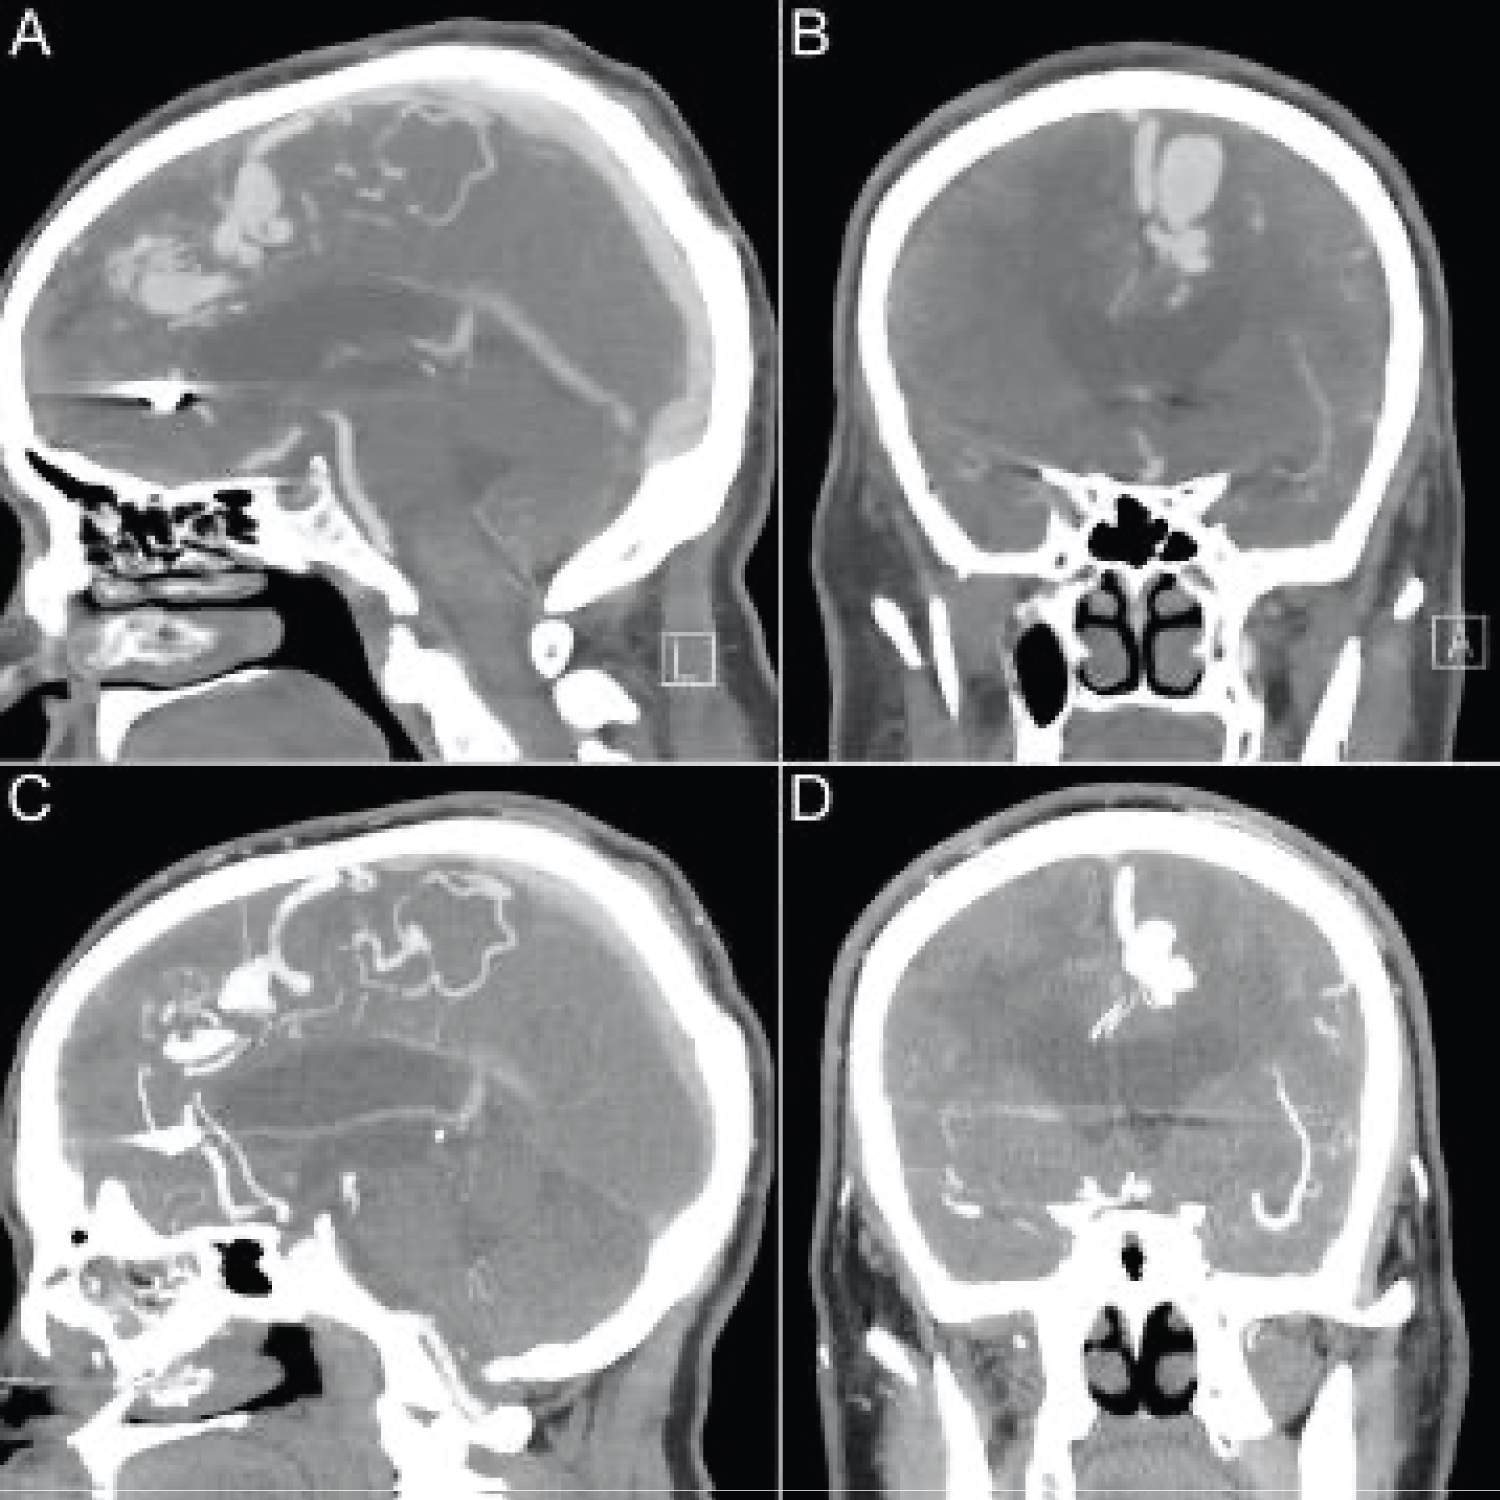

The patient's left frontal lobe AVM was first identified in 2007 with a nidus measuring approximately 21 × 20 × 21 mm. Arterial supply was predominantly from small arterial branches arising the pericallosal and callosomarginal branches of the left anterior cerebral artery. A large tortuous vein provided superficial drainage into the superior sagittal sinus. On follow up imaging, computed tomography angiography (CTA) demonstrated an interval decrease in contrast enhancement within the venous varix (Figure 1). Magnetic resonance imaging (MRI) findings were also suggestive of partial thrombosis within this venous varix and demonstrated an interval increase in vasogenic perivenous edema within the left superior frontal lobe (Figure 2). Four months later the patient underwent digital subtraction angiography (DSA), which revealed a significant decrease in nidus size, suggesting partial thrombosis of the nidus in addition to draining vein thrombosis (Figure 3). Notably, the large ectatic cortical vein draining the residual nidus was now seen to empty into multiple convexity cortical veins, whereas it had previously drained predominantly into the superior sagittal sinus, again suggestive of interval thrombosis of the draining vein.

Figure 1: CT Angiogram in November of 2017 (Sagittal [A], coronal [B]) and in October of 2020 (Sagittal [A], coronal [B]). The draining vein of the left frontal AVM is associated with a large saccular venous aneurysm. In C and D, there is an interval decrease in contrast filling of the venous aneurysm. View Figure 1